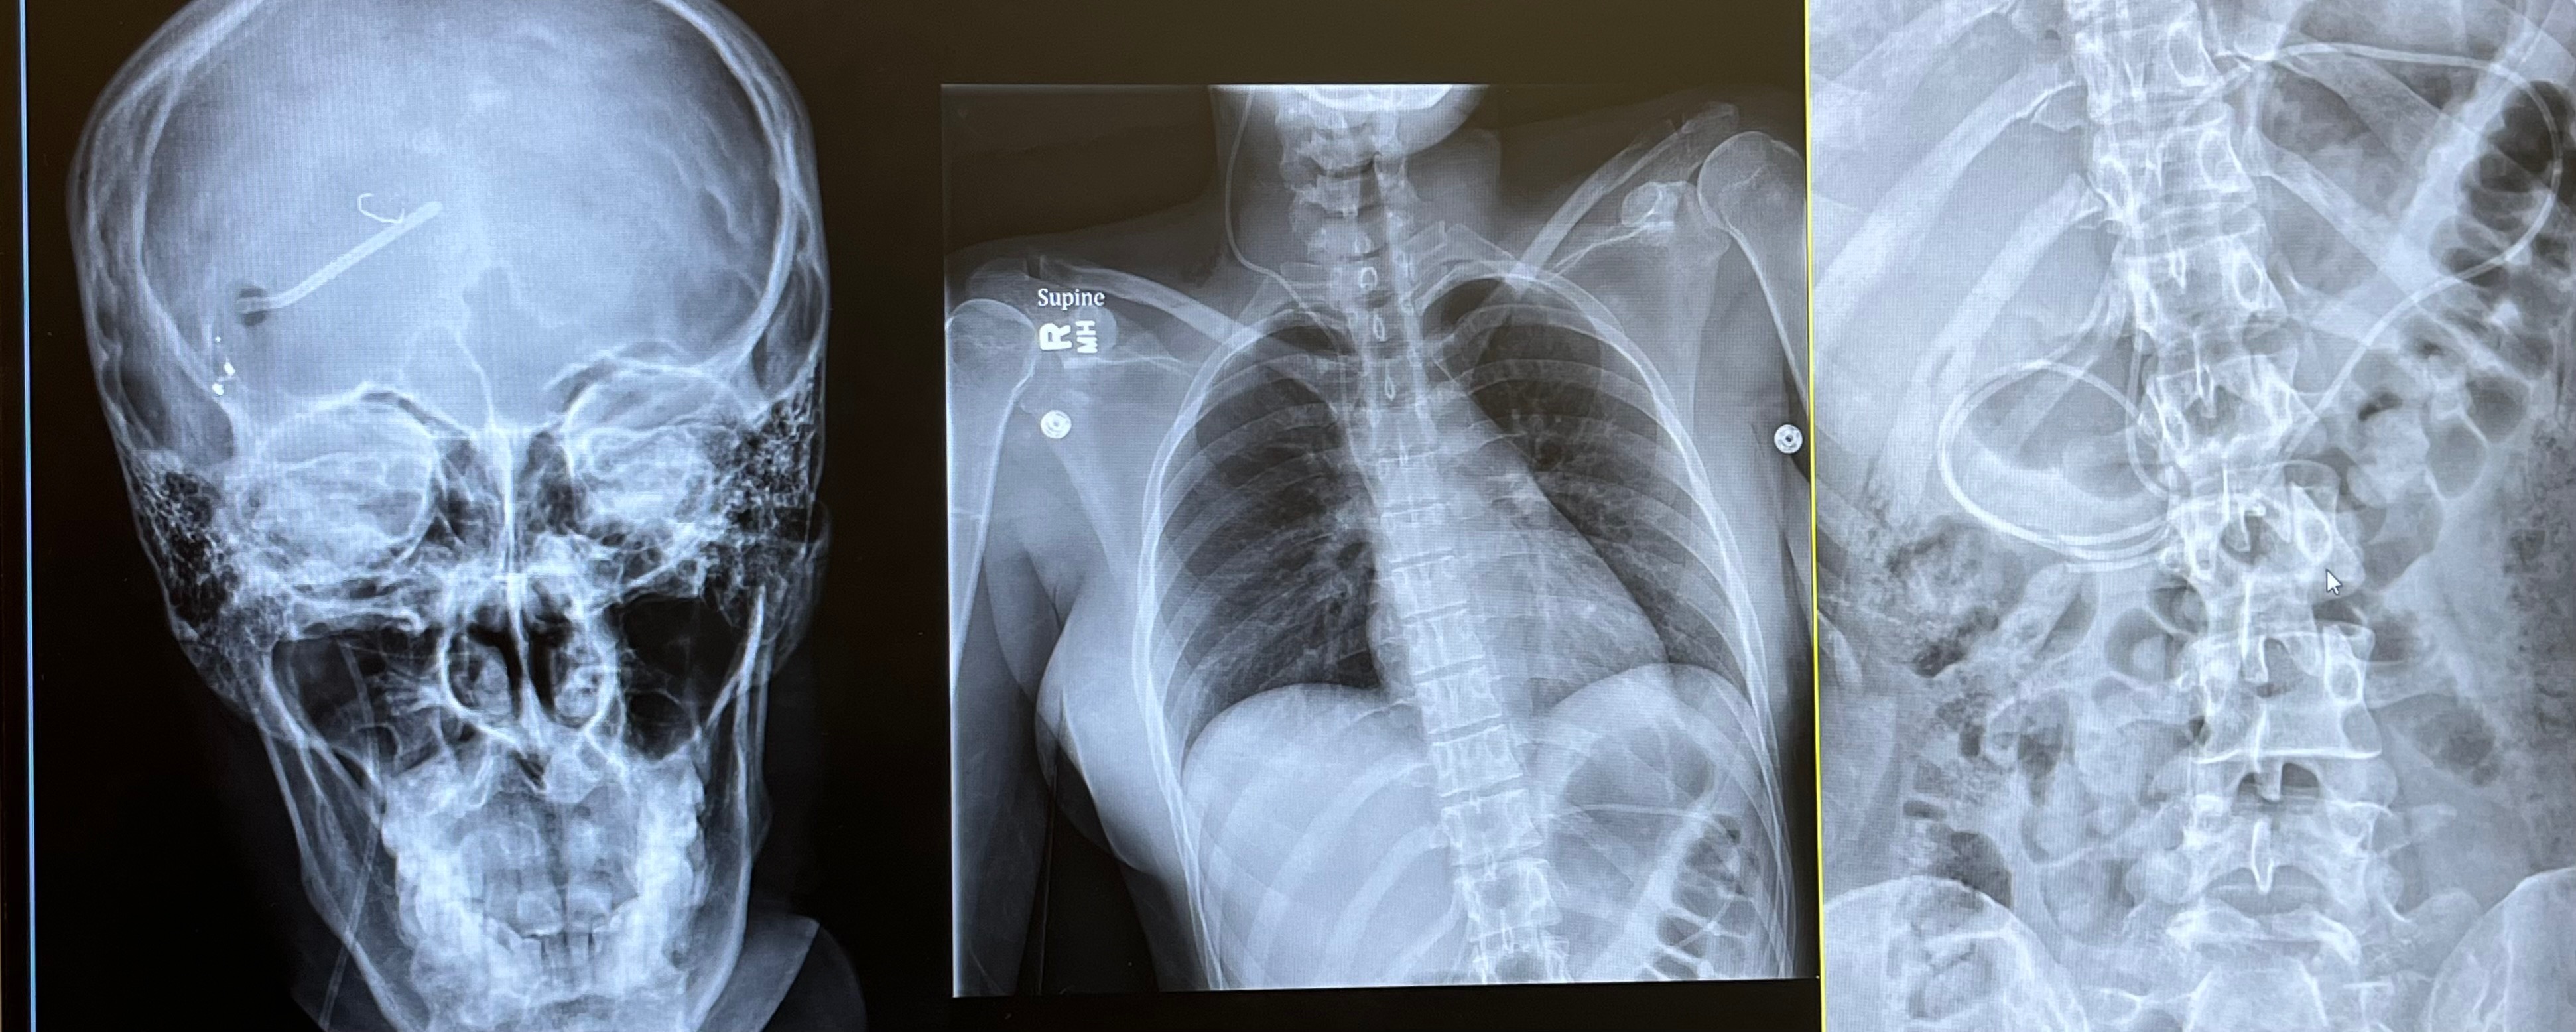

I went to Urgent Care for a CAT scan and from there, was rushed to the ICU. After MRIs, we discovered that the cerebral fluid in my brain wasn’t draining due to a pinched occipital ventricle, and the built up fluid was pushing on my eyes. This was not a problem that a lumbar puncture could fix, it required a CSF Shunt / VP Shunt. This meant that a tube would be inserted into my brain and connected to a valve attached to my skull. From there, a second tube would stretch under my skin from the valve in my skull all the way down to my stomach, acting as a drainage system for any excess fluid. So technically it was brain & abdominal surgery. People ask me when the shunt will be removed but these tools that are foreign to my body are here to stay, this isn't something that gets taken out after X amount of months. If I’m lucky, they’ll keep functioning well and future surgeries won't be necessary.